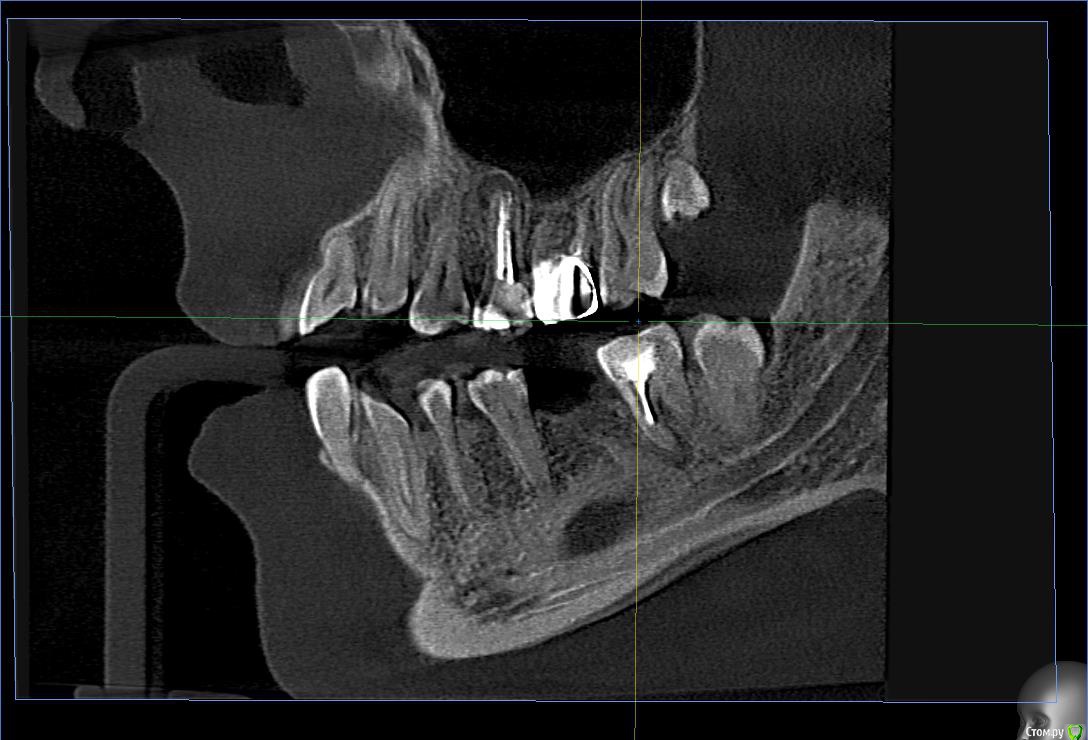

Wolfenstein Опубликовано 12 февраля, 2017 Автор Поделиться Опубликовано 12 февраля, 2017 Снимки прикрепил Ссылка на комментарий

Wolfenstein Опубликовано 12 февраля, 2017 Автор Поделиться Опубликовано 12 февраля, 2017 (изменено) вот еще один снимок Изменено 12 февраля, 2017 пользователем Wolfenstein Ссылка на комментарий

Wolfenstein Опубликовано 13 февраля, 2017 Автор Поделиться Опубликовано 13 февраля, 2017 Теперь вопрос, что стоит удалить? а что оставить? Ссылка на комментарий

Wolfenstein Опубликовано 13 февраля, 2017 Автор Поделиться Опубликовано 13 февраля, 2017 36 Ссылка на комментарий

red_butler Опубликовано 13 февраля, 2017 Поделиться Опубликовано 13 февраля, 2017 363.6 отсутствует, планируйте имплантацию и протезирование Ссылка на комментарий

Wolfenstein Опубликовано 13 февраля, 2017 Автор Поделиться Опубликовано 13 февраля, 2017 3.7 с пломбой Ссылка на комментарий

red_butler Опубликовано 14 февраля, 2017 Поделиться Опубликовано 14 февраля, 2017 что с ним?Да что же из вас жалобы клещами вытягивать приходится...с зубом - периодонтит, требуется повторное эндо лечение и последующее протезирование. Ссылка на комментарий

Wolfenstein Опубликовано 14 февраля, 2017 Автор Поделиться Опубликовано 14 февраля, 2017 Мне сказали, зуб с кистой и требуется удаление, но зуб вроде хороший, и хочется сохранить, думаю возможно ли это? Ссылка на комментарий

Паращук Роман Опубликовано 14 февраля, 2017 Поделиться Опубликовано 14 февраля, 2017 Найдите врача,что понимает толк в "лечении каналов" и с большей вероятностью вас ждет успех. Ссылка на комментарий

red_butler Опубликовано 14 февраля, 2017 Поделиться Опубликовано 14 февраля, 2017 Мне сказали, зуб с кистой и требуется удаление, но зуб вроде хороший, и хочется сохранить, думаю возможно ли это? Удалить успеете, ищите врача и перелечивайте. Ссылка на комментарий

DmitrySH Опубликовано 16 февраля, 2017 Поделиться Опубликовано 16 февраля, 2017 Ну и 24 кариес лечить, 25 ревизия каналов, 26 непонятно что с ним Ссылка на комментарий

Wolfenstein Опубликовано 28 февраля, 2017 Автор Поделиться Опубликовано 28 февраля, 2017 26 - удалил, это вкладка, 27 - нормальный , 28 - нет, он спрятался за деснами, там пусто Ссылка на комментарий